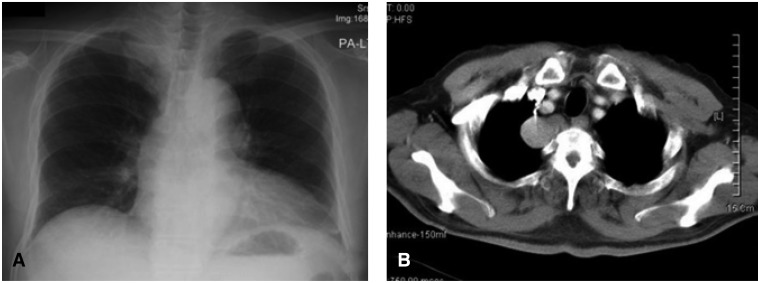

A 64-year-old man was referred to the pulmonary department of Korea University Ansan Hospital for an evaluation of a lung mass. He had received a medical checkup 1 month previously, when the mass-like lesion was incidentally found on plain chest X-ray. He was asymptomatic and had well controlled hypertension and diabetes; he also had a smoking history of 40 pack-years. On physical examination, no palpable lymphadenopathy or other abnormality was noted. His hemoglobin, white cell count, platelets, urea and electrolytes, glucose, liver function tests, and serum calcium were normal. The plain chest X-ray revealed a smooth marginated 3×4 cm sized mass-like lesion in the right upper mediastinal area (Figure 1A). Chest computerized tomographic (CT) studies, performed after the intravenous administration of a contrast agent, revealed a 2.5×2 cm sized, well defined, bilobed, homogeneously enhancing mass lesion in the right upper posterior mediastinum (Figure 1B). No definite evidence of bony erosion of the thoracic vertebrae was observed. On magnetic resonance imaging (MRI), the tumor was visualized as a homogeneous signal intensity mass with a signal intensity similar to muscle on T1-weighted images, whereas on T2-weighted images, the signal intensity was moderately higher than that of muscle. Moderate heterogeneous enhancement was noted with gadolinium-enhancement (Figure 2).

Figure 1

Plain chest roentgenography (A) showed a smooth, marginated 3×4 cm sized mass-like lesion on the right upper mediastinal area. Chest computed tomographic (CT) with enhancement (B) revealed a 2.5×2 cm sized, well defined bilobed, homogeneously enhancing mass lesion, in the right upper posterior mediastinum. No definite evidence of bony erosion of thoracic vertebrae was noted.